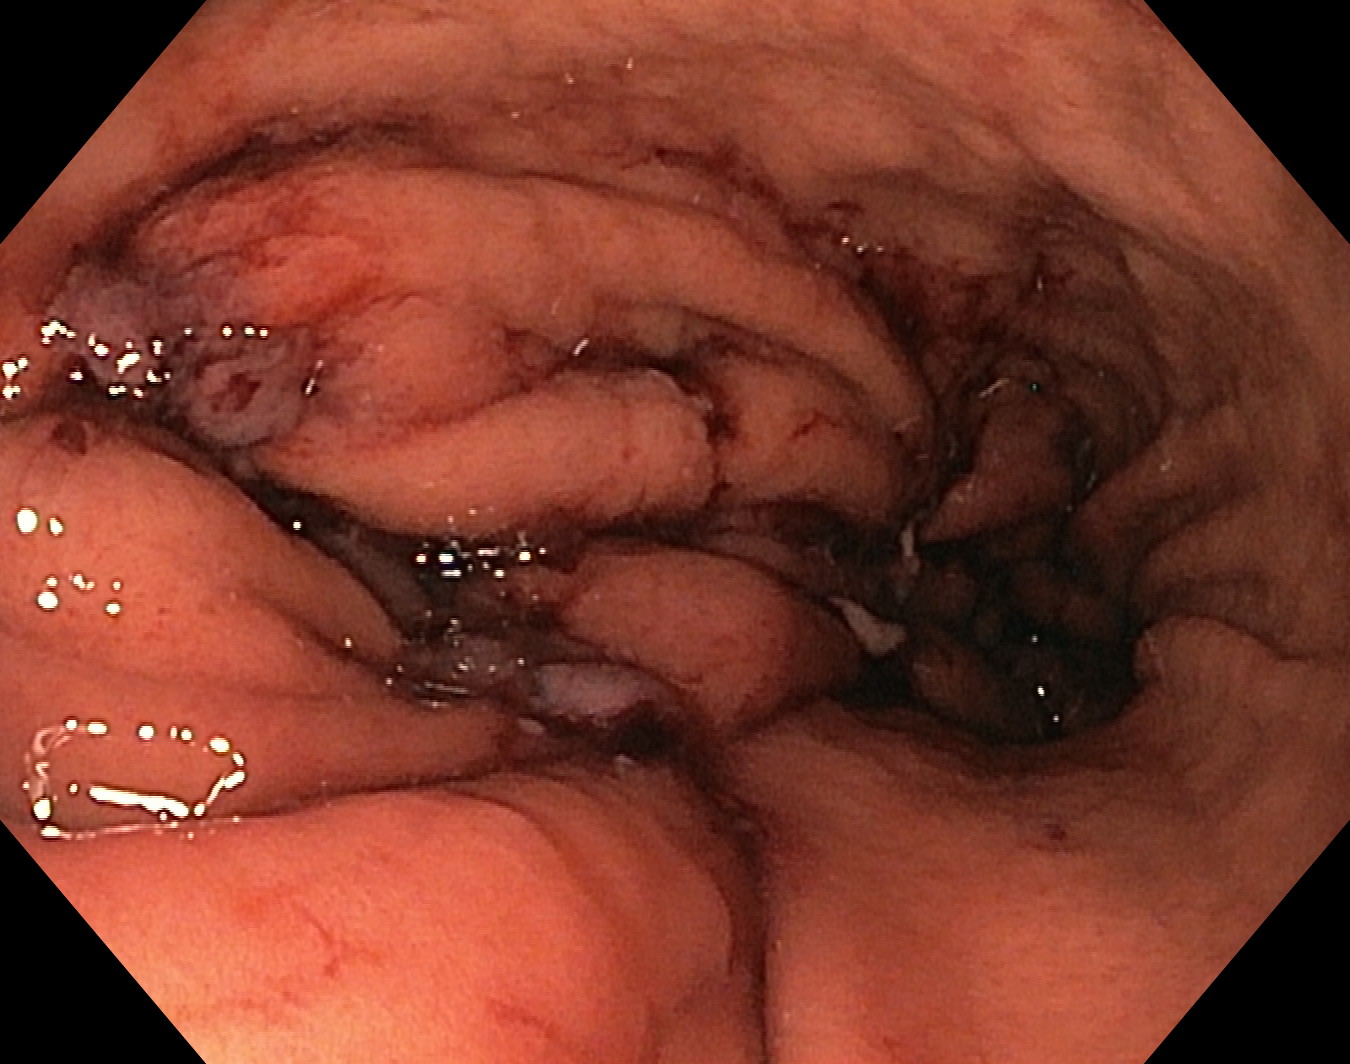

После предварительного обследования произведена операция: ESG + АПК (APC) свода; всего использовано 6 швов, время процедуры ≈ 120 минут.

Под видеоконтролем выполнена эндоскопическая рукавная гастропластика: сшивание стенок желудка при помощи аппарата Overstitch Boston Scientific по длине тела с целью уменьшения объёмов съедаемой пищи.